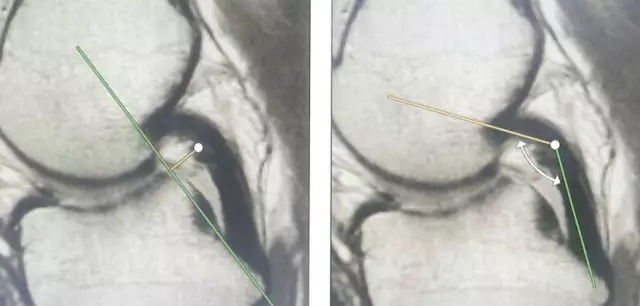

Blumensaat 角(-1.6度)

大于9-15度视为异常

前交叉韧带与胫骨平台角度(56度)

小于45-50度视为异常

后交叉韧带折弯度

弧度:0.19厘米,角度:114-123度